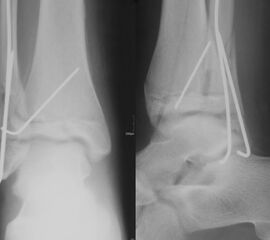

Findet sich eine Dislokation der Wachstumsfuge erfolgt nach Reposition eine K-Drahtspickung. Die postoperativ angelegte Gipsschale wird nach Abschwellung entfernt und ein Unterschenkelgips für 4 Wochen angelegt.

Nach Gipsabnahme können die Drähte entfernt und das Sprunggelenk zunehmend aufbelastet werden.